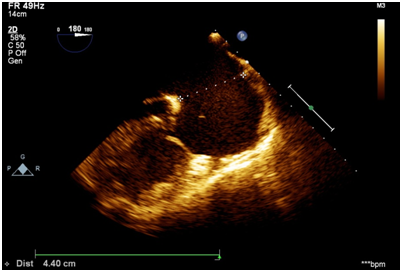

The 2D-Echo showed ostium secundum atrial septal defect of size 4.4cm with a bidirectional shunt. RA and RV dilated. This was confirmed by TEE. (Figure 3)